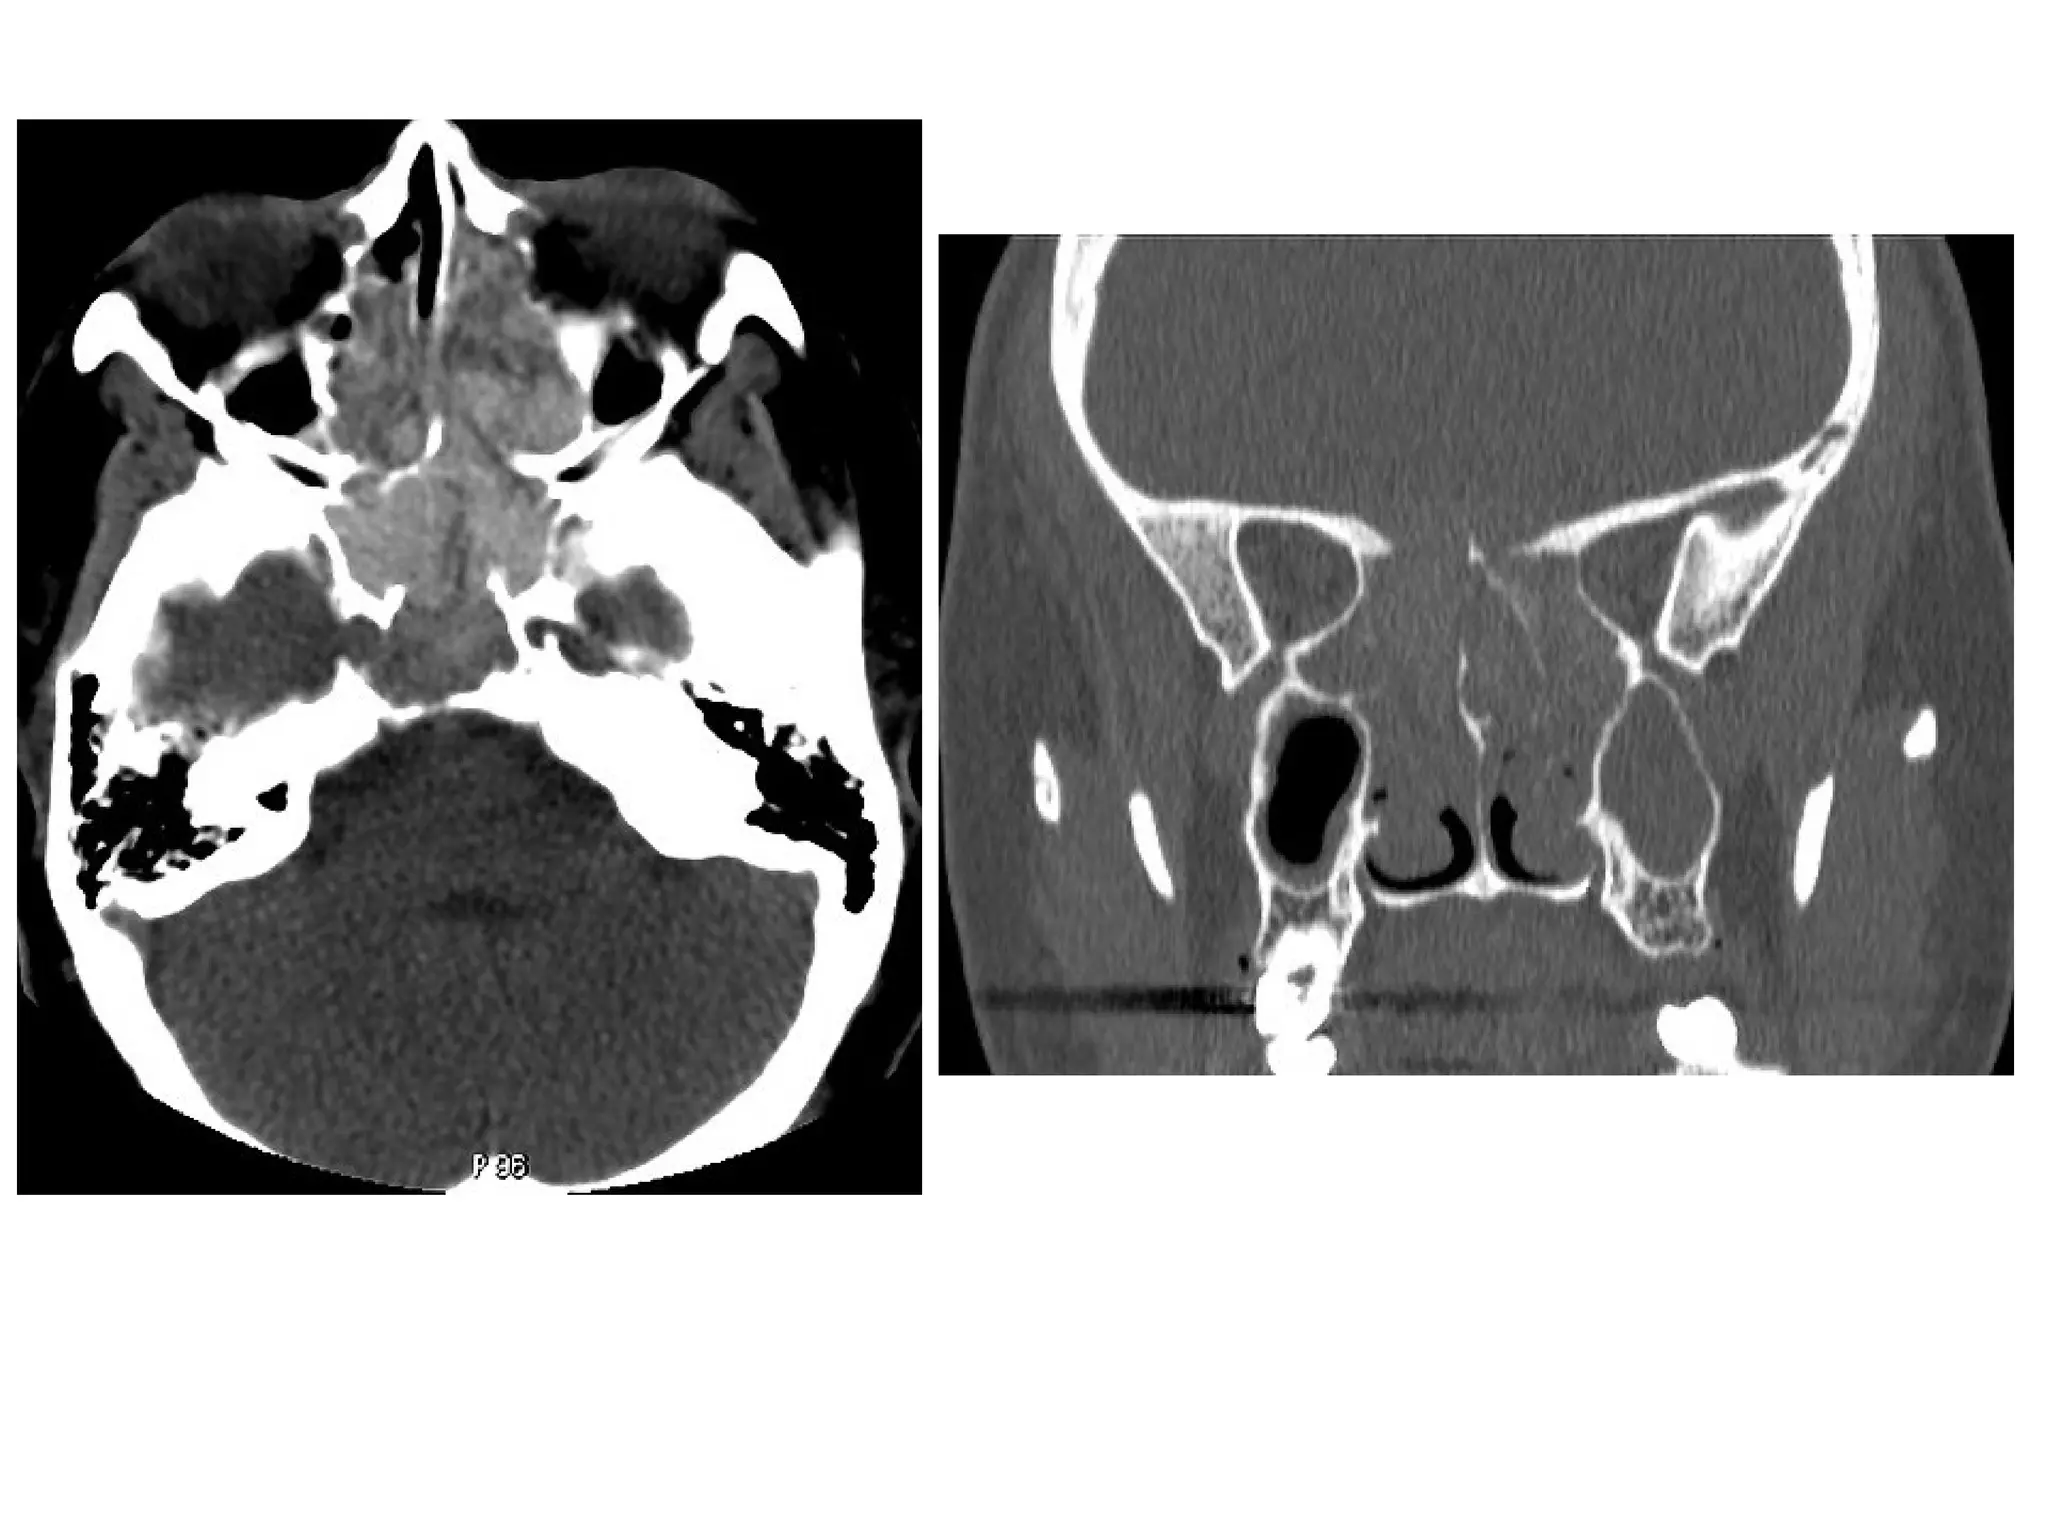

Acute invasive zygomycosis in a 59-year-old man, (a) Axial unenhanced CT scan shows

increased attenuation in the right anterior and posterior ethmoid air cells and right

sphenoid sinus with soft-tissue thickening in the orbital apex (arrow), (b) Coronal

unenhanced CT scan shows destruction of the medial wall and floor of the right orbit

and disease extension into the orbit (arrows), (c) Axial unenhanced CT scan obtained

caudad to a shows destruction of the posterior wall of the right maxillary sinus and

obliteration of the periantral fat plane immediately posterior to the sinus (arrows)